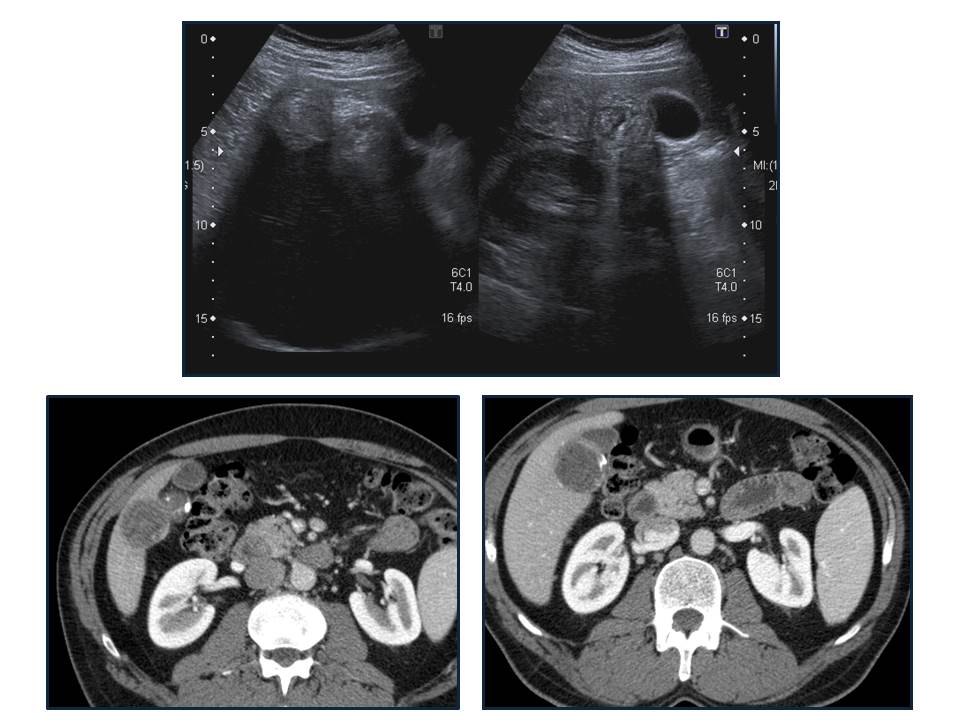

Para ver otro ejemplo:

- Ecografía: La calcificación suele verse entre el 20-30% de los quistes. La pared suele verse como dos líneas hipoecogénicas seperadas por otra hiperecogénica , que es la capa intermedia.. La ecografía es la mejor técnica para identificar las capas del quiste.

- TC: Tiene mayor S y E para la valoracion del quiste hidatídico. Se usa cuando la ecografía no nos proporciona un resultado óptimo por obesidad, interposición de gas, cambios postquirúrgicos en la pared abdominal, deformidades, etc… La administración de contraste no es necesaria a menos que se sospechen complicaciones, especialmente la infección o la comunicación con la vía biliar. Los hallazgos por TC son similares a los de ultrasonido, como son la densidad líquido en el interior del quiste, vesículas hijas en la perifería del quiste mayor o madre o calcificación de pared. La pared del quiste muestra alta atenuación inclusive sin contraste y sin calcificación.

Elevación del hemidiafragma derecho una lesión quistíca de gran tamaño en segmento VII que continua con el segmento VI. Que pierde plano de clivaje con espacio pararrenal anterior